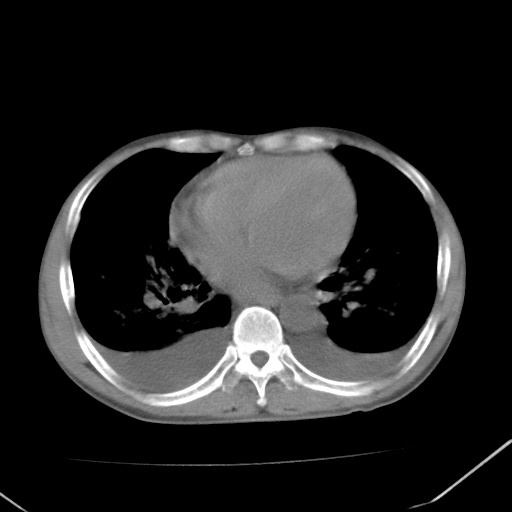

左心房增大,考虑心衰,肺水肿。

心影增大密度略低,双肺磨玻璃样高密度影及双侧胸腔积液,考虑心功能不全继发双肺肺水肿及双侧胸腔积液。心影密度略低,考虑贫血所致。